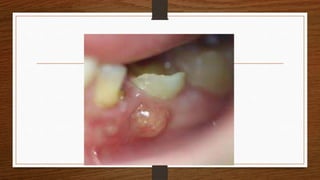

Abscess

• Definition: localized area of suppuration, characterized by cavity formation

full of pus.

• Cause: the causative organism is commonly staphylococcus aureus which

releases coagulase enzyme leading to localization of infection.

• An abscess may be discharged to

the surface due to increased

pressure inside or may require

drainage by the surgeon. Due to

tissue destruction, resolution does

not occur but instead healing by

fibrous scarring takes place.